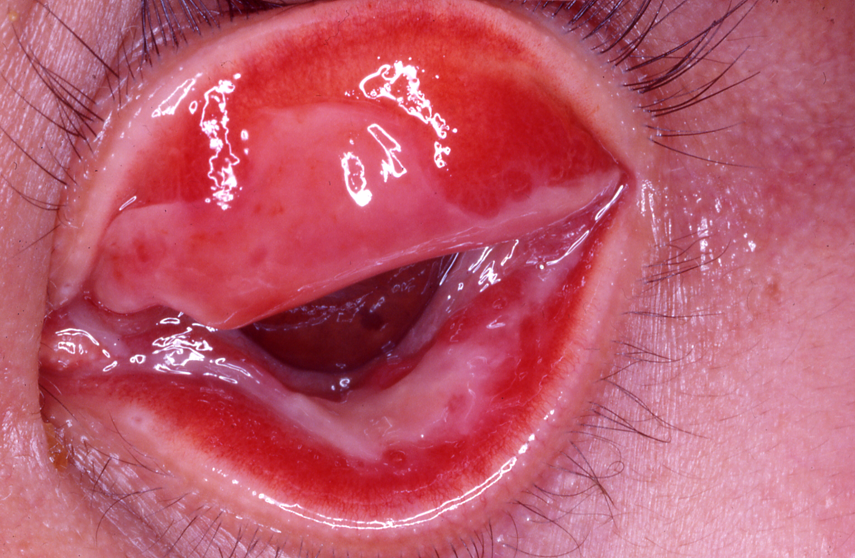

図15 偽膜性結膜炎

上下の瞼結膜に偽膜形成がみられる。厚くなるとこのような白いゴム様の外観を呈する。アデノウイルス結膜炎の例。単純ヘルペス、新生児クラミジア結膜炎でもみられることがある。